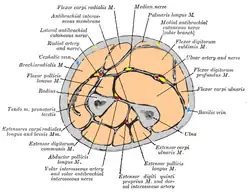

Deep muscles of the posterior forearm Cross-section through the middle of the forearm.

Cross-section through the middle of the forearm. Bones of the forearm - ulna (left) and radius (right)

The forearm contains many muscles, including the flexors and extensors of the wrist, flexors and extensors of the digits, a flexor of the elbow (brachioradialis), and pronators and supinators that turn the hand to face down or upwards, respectively. In cross-section, the forearm can be divided into two fascial compartments. The posterior compartment contains the extensors of the hands, which are supplied by the radial nerve. The anterior compartment contains the flexors and is mainly supplied by the median nerve. The flexor muscles are more massive than the extensors because they work against gravity and act as anti-gravity muscles. The ulnar nerve also runs the length of the forearm.[3]

The radial and ulnar arteries and their branches supply the blood to the forearm. These usually run on the anterior face of the radius and ulna down the whole forearm. The main superficial veins of the forearm are the cephalic, median antebrachial and the basilic vein. These veins can be used for cannularisation or venipuncture, although the cubital fossa is a preferred site for getting blood.